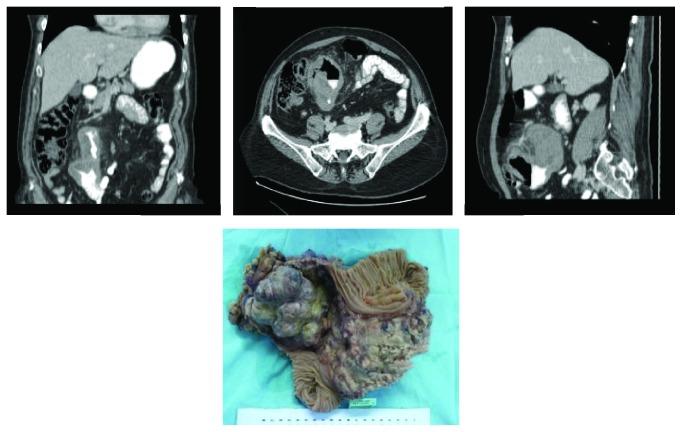

Metastatic involvement of gastrointestinal tract from breast cancer is a rare event. We report the case of a 61-year-old woman presenting with bowel obstruction, related to metastasis of a primary breast cancer she had 12 years earlier (a triple-negative invasive ductal carcinoma treated with surgery and chemotherapy). Bowel obstruction was caused by a 20-centimeter tumor in the jejunum, involving also the transverse colon. The patient underwent en bloc resection of tumor with jejunum and transverse bowel segment and received adjuvant chemotherapy with carboplatin and paclitaxel. Twenty months later, she was alive without disease recurrence.

乳腺癌转移至胃肠道是一种罕见的情况。我们报告了一例61岁女性,因肠梗阻就诊,该肠梗阻与她12年前患的原发性乳腺癌转移有关(原发性三阴性浸润性导管癌,接受了手术和化疗)。肠梗阻由空肠内一个20厘米的肿瘤引起,该肿瘤还累及横结肠。患者接受了肿瘤与空肠及横结肠段的整块切除,并接受了卡铂和紫杉醇辅助化疗。20个月后,她存活且无疾病复发。